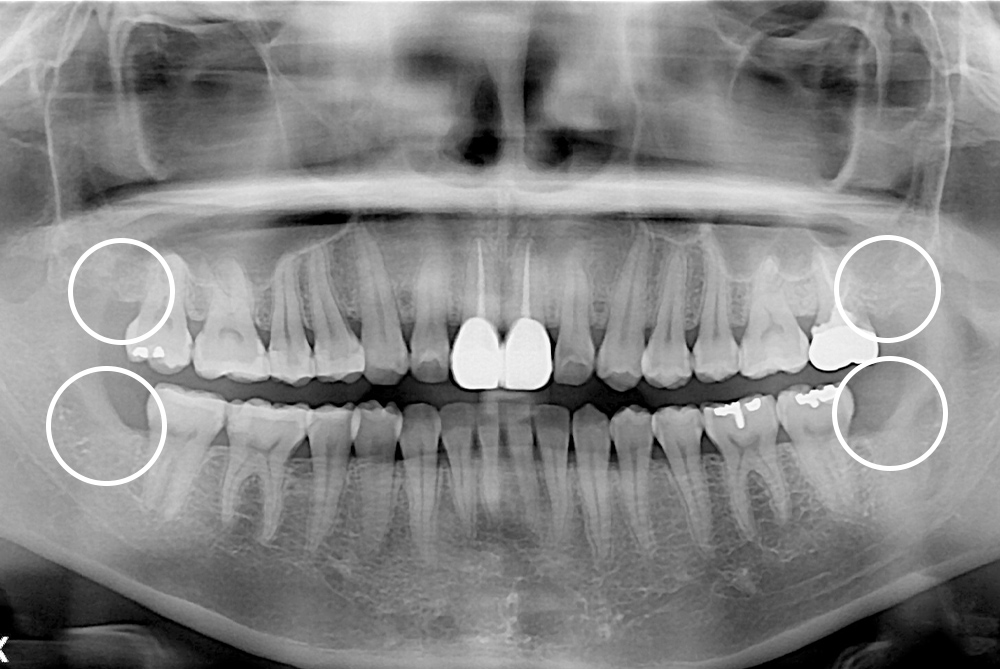

[사랑니] 매복 사랑니 발치

치료후 : 2020-09-11

세종치과는 구강악안면외과학 박사이신 원장님이 발치하는 치과입니다.